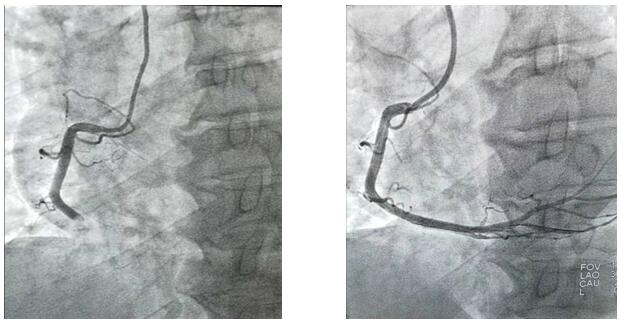

2019年10月1日凌晨1點左右,興平市人民醫院將一位急性心梗病人送至我院,患者胸痛5小時并伴有大汗,心電圖顯示ST段呈弓背向上型抬高,出現寬而深的Q波和T波倒置。心肌酶及肌鈣蛋白升高。心血管病院值班二線立即通知導管室值班醫生。“導管室已啟動”,一場與死神的博弈即將開始,醫護人員“飛毛腿”式趕到導管室,護士開始了準備工作,“液體已配好、除顫儀處于備用狀態、急救藥品準備完畢”的同時,隨著技師“趕快帶病人”。醫護人員穿上近30斤重的鉛衣、洗手、戴口罩,一場沒有硝煙的戰爭正式開始了,消毒、穿刺、造影.....手術緊張而有序的進行著,經過一小時左右的奮力搶救,病人終于脫離了危險。安全送至CCU后,醫護人員此時已經筋疲力盡,身上的衣服也已經濕透,但大家還是會共同探討手術的過程。

凌晨3點,手術室終末消毒工作剛剛結束,“滴滴滴……”胸痛中心來電,啟動導管室,醫護人員再次穿上鉛衣沖向屬于自己的特殊戰場……10月1日、10月2日、10月3日、10月4日、10月5日、10月6日,我們完成PTCA支架置入術、冠狀動脈內溶栓術、PTCA腔內成型術、臨時起搏器置入術、冠狀動脈內左室造影術及冠狀動脈內血管造影術共計心臟介入手術35例。我們永不停息的穿梭與手術間,平凡的本職工作中,與死神賽跑.....挽救了無數名生死垂危的患者,解除患者病痛的同時,還您一個完整、幸福的家!